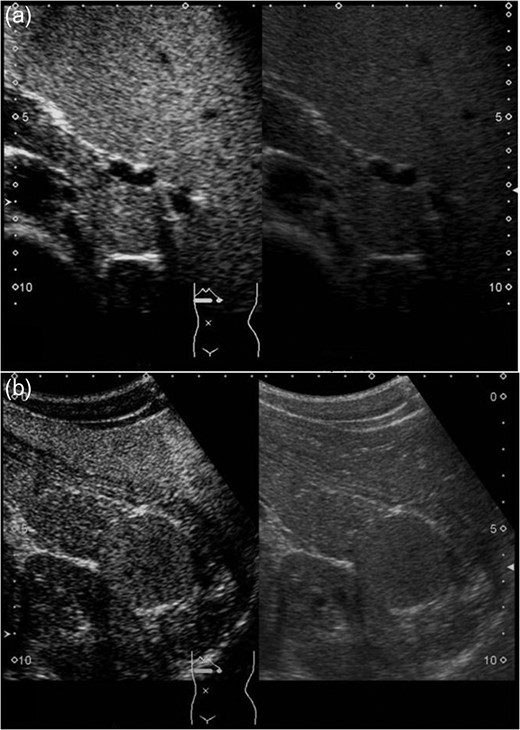

A 16-year-old boy was admitted with a rapidly growing pancreatic mass. He had received a diagnosis of HS based on the following: the need for a blood transfusion to treat anemia after birth, a history of hemolytic anemia, and a family history of HS. He had often undergone medical examinations for anemia and jaundice in junior and senior high school. When he was 15 years old, he visited our hospital because of the rapid onset of jaundice. Radiological examinations, such as computed tomography (CT) (Fig. 1a–c) and magnetic resonance imaging (MRI) (Fig. 2a–c), showed a huge spleen and a 2-cm mass near or in the pancreatic tail. Sonazoid-enhanced ultrasonography showed hypervascularity in the mass, which appeared to be located near the pancreatic tail and raised suspicions about an accessory spleen (Fig. 3a). The patient underwent a successful splenectomy by laparotomy, but the mass found on the preoperative examination could not be found by inspection and intraoperative ultrasonography (Fig. 4a and b). The mass grew rapidly to 4 cm one year after splenectomy, as shown on the radiological examinations (Figs 1d–f, 2d–f and 3b), but a recurrence of HS with anemia or jaundice did not develop. However, he underwent successful laparoscopic surgery to aid in the differential diagnosis. After the adhesions of the omentum to the abdominal wall were detached, the laparoscopic ultrasonogram revealed the mass in the pancreatic tail. He underwent laparoscopic distal pancreatectomy (Fig. 4c and d), and he had no clinical symptoms or signs of local infection or sepsis. A CT on the ninth postoperative day showed a small peripancreatic collection (Grade B: the clinical grading of postoperative pancreatic fistula). He was discharged on the 11th postoperative day. The resected specimen revealed the intrapancreatic mass that was covered with pancreatic tissues, and the intrapancreatic mass was an accessory spleen (Fig. 4e).

Sonazoid-enhanced ultrasonography Presplenectomy enhanced ultrasonography shows hypervascularity in the mass, located near the pancreatic tail and suspicious for an accessory spleen. The mass grows rapidly to 4 cm by 1 year after splenectomy (a: before splenectomy, b: after splenectomy).